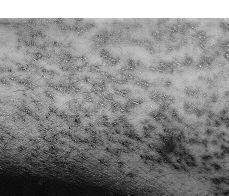

Varón de 44 años de edad, sin antecedentes médicos de interés, que consultó por un cuadro clínico asintomático de 10 años de evolución consistente en pápulas eritemovioláceas que adoptaban una disposición lineal y reticulada, a nivel de brazos y piernas, predominando en pliegues de flexión (axilas, fosas antecubitales, huecos poplíteos e ingles) (Figs. 1 y 2). El paciente presentaba además una erupción eritemoescamosa a nivel de región interciliar y surcos nasogenianos clínicamente similar a un eccema seborreico.

FIG.1.--Lesiones eritemovioláceas, hiperqueratósicas, afectando simétricamente áreas flexoras de las extremidades superiores.